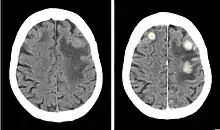

Iobitridol (trade name Xenetix) is a pharmaceutical drug used as an iodine-based radiocontrast agent in X-ray imaging.[1] It is injected into blood vessels, joints, or body cavities such as the uterus, and filtered out by the kidneys.[2] Its most common adverse effect is nausea. Severe allergic reactions are rare.[1][2]

Iobitridol is used for intravenous urography (imaging of the urinary system via a vein), angiography (imaging of blood vessels), angiocardiography (heart and coronary arteries), arthrography (joints), hysterosalpingography (uterus and fallopian tubes), and imaging of the cranium and the whole body.[2] It is approved for use in adults and children.[5]

Iobitridol is an iodine-containing radiocontrast agent.[2][5] The iodine atoms readily absorb X-rays, resulting in better contrast in radiography images.[9] The quality of images made with this drug is equally good as with other low– or medium–osmolarity iodinated contrast agents such as iopamidol or iohexol.[5]